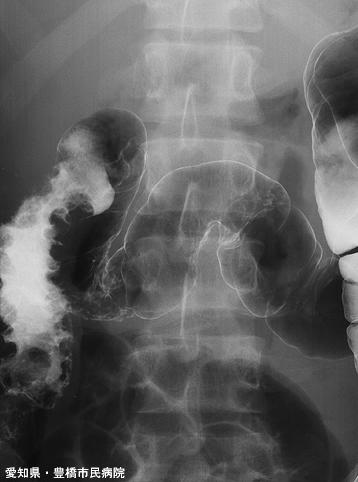

Enfermedad Intestinal de tipo inflamatorio (Sospecha de Enfermedad de Crohn) acompañado de lesión en esófago (Caso presentado por: Hospital Municipal de Toyohashi, Prefectura de Aichi)

Enfermedad Inflamatoria - Ulcerativa/Enfermedad de Chohn

colon/lesión que abarca dos o más regiones del colon

Rayos X

40 -